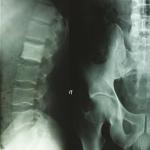

Lymphome anaplasique à grandes cellules ostéocondensant

Un patient âgé de 35 ans, sans antécédents pathologiques particuliers, consulte pour des douleurs inflammatoires de l...